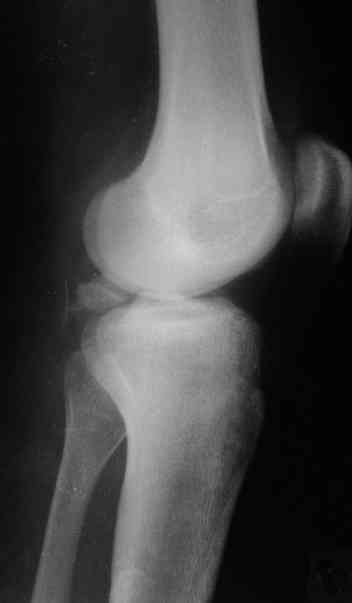

Based on the images ( it would be nice to have axial cuts),it seems to be posteromedial fragment, almost all the way into

posterior portion of the tibial eminance.

На основании небольшого личного опыта (4 пациента с отрывным переломом задне-верхнего края большеберцовой кости) и данных литературы оптимальным считаю задний доступ, упомянутый David P. Zamorano.

В 3 из 4 случаев мы применили винт, проведенный ретроградно по аналогии с фиксацией заднего края большеберцовой кости при переломах в

области голеностопного сустава. В прищепке рентгенограммы одного из наших пациентов до операции и спустя полгода. Остальные 3 наблюдения